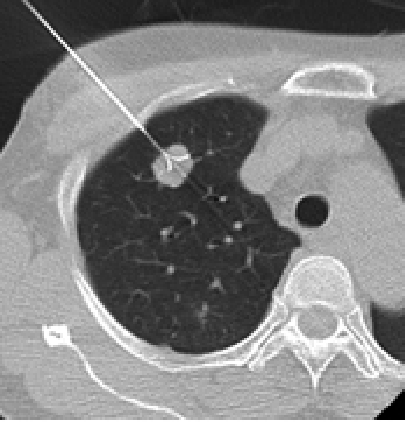

症例1

右原発性肺がんの症例ですが、ラジオ波治療を行うと、約半年後には腫瘍は死滅し瘢痕状となっています。

治療前

治療中